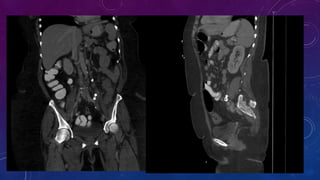

• Small well-defined round osseous lesions in the left

side of the abdomen, adjacent to midline represent

calcified lymph node in the para-aortic and left

common iliac groups, also visualized on the

corresponding CT.